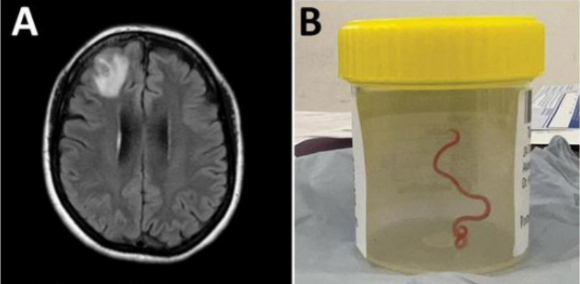

이후 수술을 집도하던 신경외과의 하리 프리야 반디 의사는 수술 도중 충격적인 장면을 목격했다. 환자의 뇌에서 8㎝ 길이의 기생충을 발견했기 때문이다. 또 그 기생충은 뇌에서 나와서도 살아서 꿈틀대고 있었다.

호주 연방과학산업연구기구(CSIRO)는 이 기생충을 '오피다스카리스 로베르시'라는 회충으로 확인했다고 밝혔다. 이 회충은 주로 비단뱀 체내에서 발견되며, 사람 몸에서 발견된 건 이번이 처음이다.